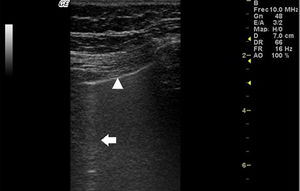

In ILD, there is a decrease in acoustic impedance between the lung air and the soft tissues of the chest wall, because part of the space initially occupied by air volume is replaced by infiltration of inflammatory cells or connective tissue, leading to pleural line disturbances and vertical artefacts called "B-lines". B-lines are indicative of increased subpleural lung density prior to consolidation and may be caused by the presence, not exclusively, of interstitial disease.25 The pleural line becomes irregular and thickened and may appear blurred and fragmented. B-lines are shown as vertical hyperechoic streak-like artefacts arising from the pleural line and extending to the end of the screen without fading, blurring the A-lines, and moving synchronously with the pleural sliding. The presence of multiple B-lines is the defining ultrasound sign of "interstitial syndrome".26Fig. 2 shows a CT scan of a patient with RA and ILD; Fig. 3 shows the ultrasound findings.

Lung ultrasound performed on the same patient as in Fig. 2 with GE Logiq 3 equipment, with 10–14 MHz multifrequency linear transducer, with the patient in a seated position and transducer in longitudinal direction. The arrow points to a B line. The triangle points to the pleural line, which is irregular in appearance. Note the absence of A lines.